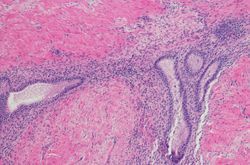

Similar to traditional IHC, mIHC is based on the interaction between an antibody and its target antigen. Primary or secondary antibodies conjugated to a chromogen or fluorescent dye are used for detection.

Chromogenic mIHC

Chromogens are soluble substrates that form colored precipitates in the presence of enzymes. For high abundance molecular targets, chromogenic mIHC may employ primary antibodies that are directly conjugated with different chromogens. Alternatively, the primary antibodies may interact with chromogen-conjugated secondary antibodies to enable signal amplification for low abundance targets. Multiple staining cycles are performed if multiple proteins are to be visualized in a single tissue section.

Fluorescent mIHC

Fluorescent dyes such as FITC, TRITC, Cy3, and Cy5 are used to visualize protein targets. Conventionally, each fluorophore is imaged separately and the individual images are then merged together to evaluate localization of multiple proteins. Alternatively, multispectral analysis can be performed, wherein representative emission spectra of individual fluorophores are saved. The intensity of fluorescent targets is then compared against this multispectral library during quantification. To avoid multiple rounds of antibody staining, imaging, and fluorophore bleaching or antibody removal, mass spectrometry-based approaches have been optimized. These employ rare earth metalconjugated antibodies for immunostaining, followed by high-frequency laser ablation and mass spectrometry for increased subcellular resolution2.

Tyramide signal amplification (TSA)

TSA is an enzyme-mediated detection method that uses the catalytic activity of peroxidase enzyme to enhance fluorescence labeling of target proteins. The enzyme catalyzes the binding of tyramide-labeled fluorophores to tyrosine residues on the target protein. With fluorophores deposited on several tyrosine residues around the antibody complex, an amplified signal is produced. This technique allows the use of multiple antibodies raised in the same host species without risk of cross reactivity. Although TSA can be applied to both chromogenic and fluorescent mIHC, the latter is preferred because the fluorescent spectrum allows more dyes to be introduced.

Similar to other molecular biology techniques like gene expression profiling and flow cytometry, mIHC provides information on multiple cellular targets in sparse samples. However, mIHC offers the added advantage of preserving tissue architecture, providing a spatial overview of protein co-localization and interactions, often at subcellular resolution.

Chromogenic mIHC enables detection of low abundance proteins with high sensitivity. The colored precipitates formed produce more durable staining, allowing long-term storage without signal degradation. Fluorescent mIHC combined with tyramide signal amplification, enables detection of a large array of proteins, even those with low levels of expression. It is also an ideal tool for measuring protein co-localization.